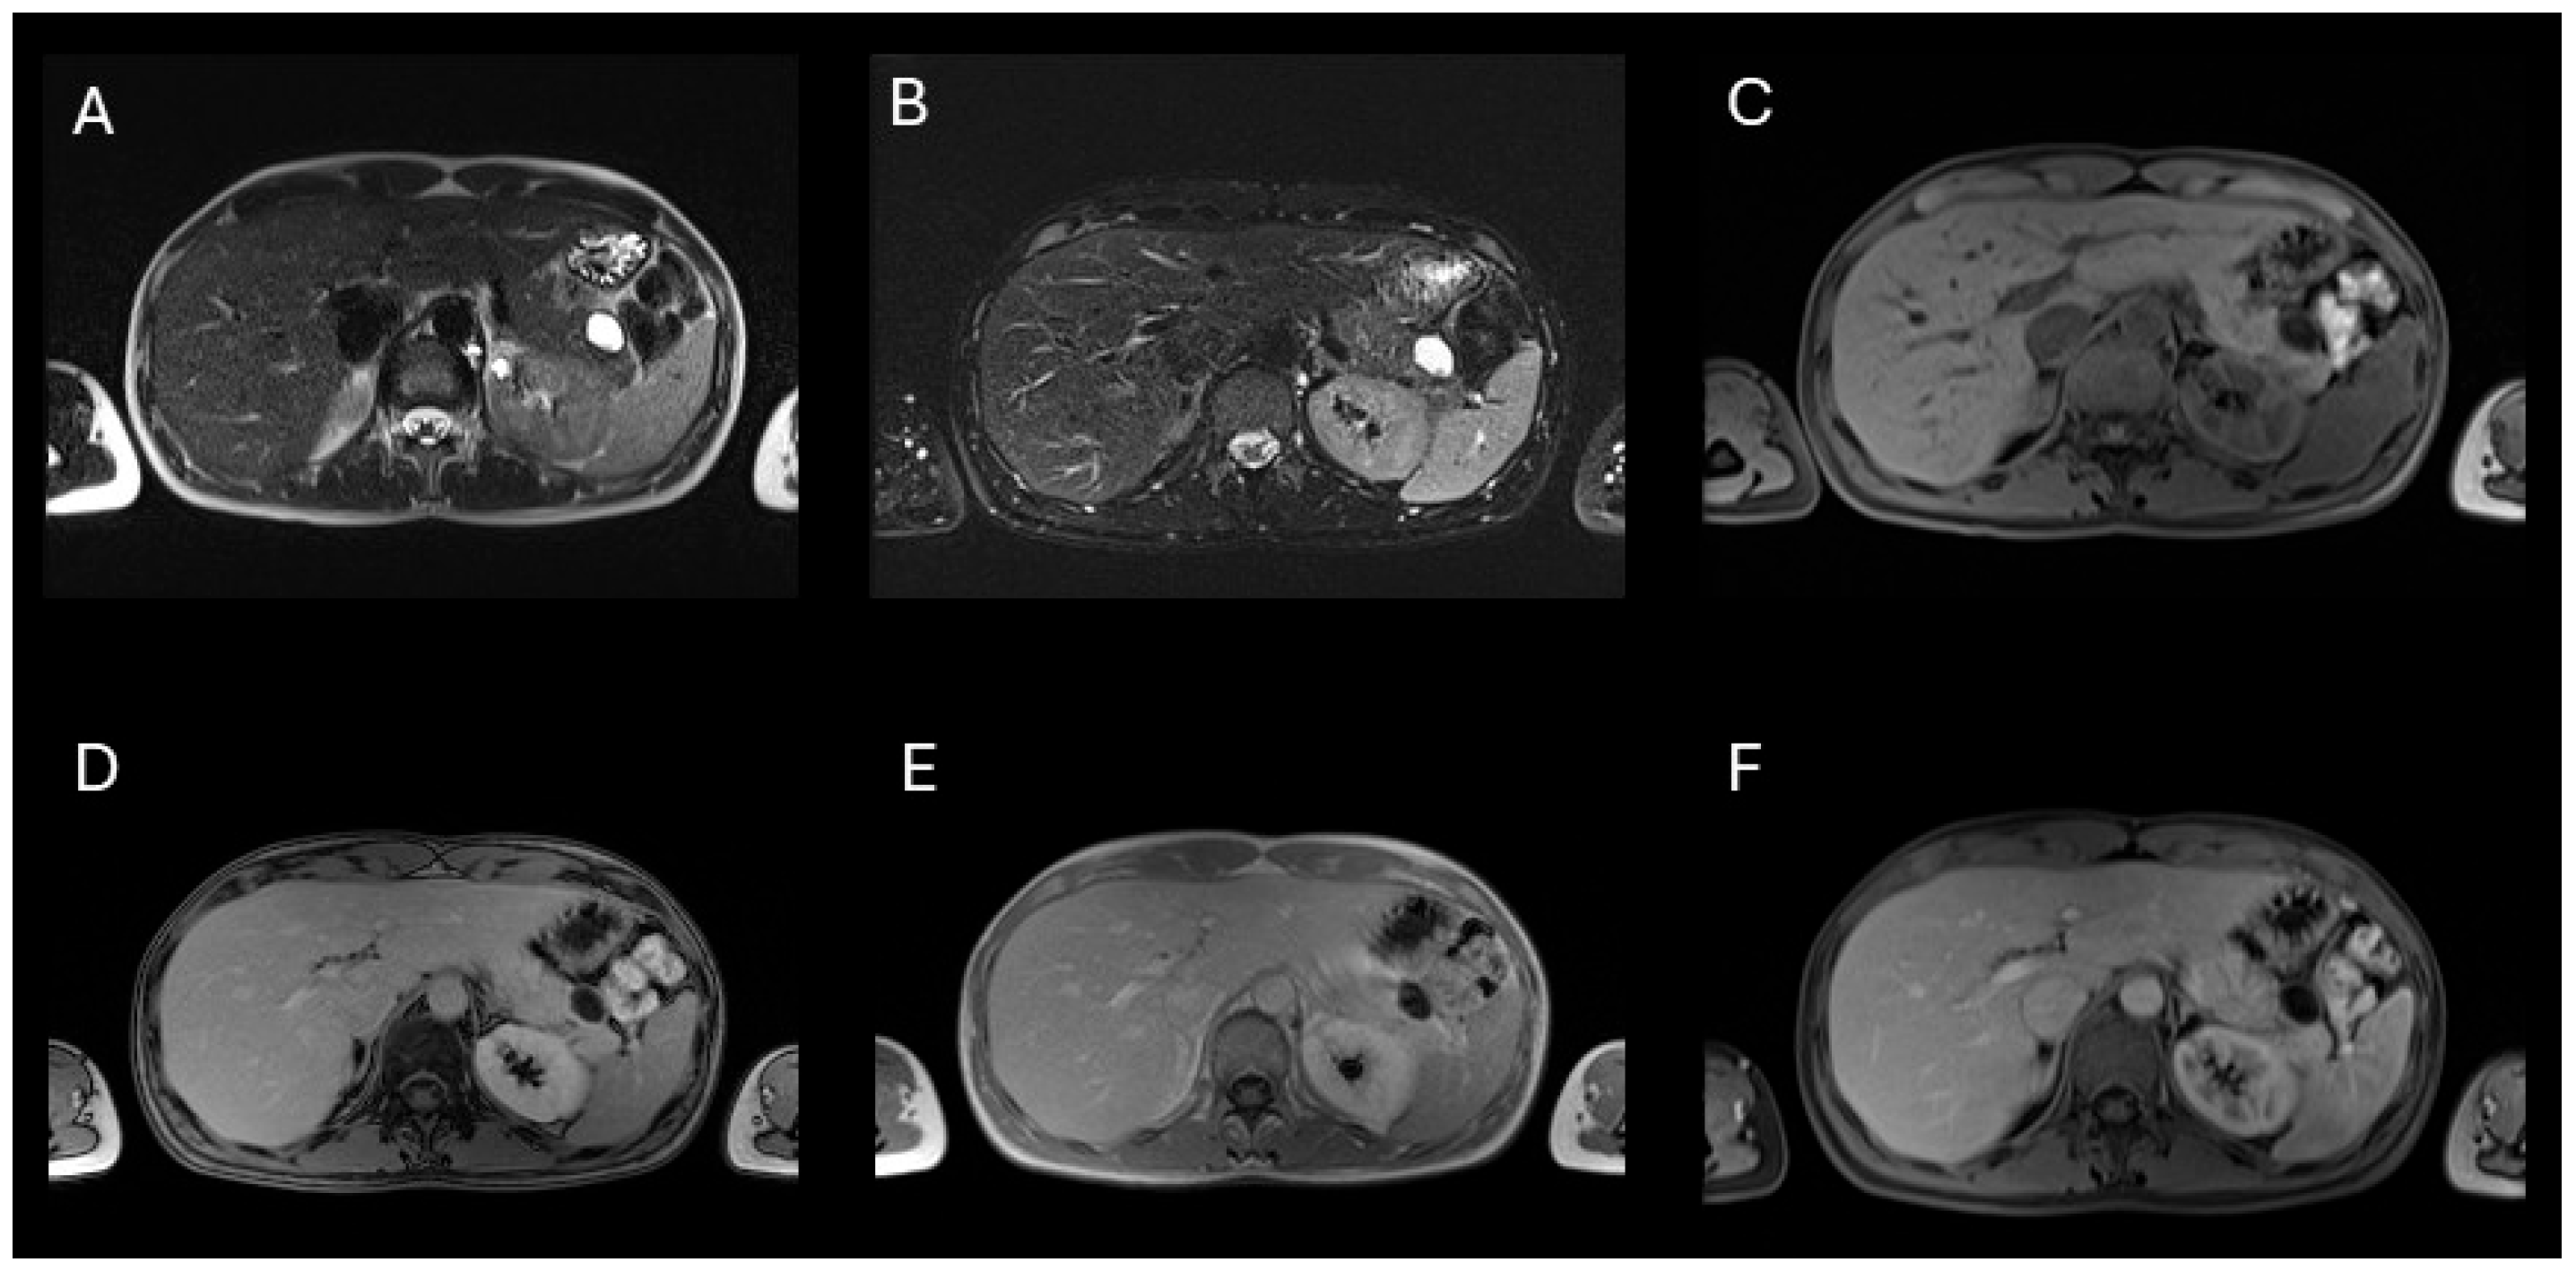

Background: Pancreatic hamartoma (PH) is an exceptionally rare, benign, mass-forming lesion accounting for less than 1% of all pancreatic tumors. Its rarity and non-neoplastic nature contribute to significant diagnostic challenges, often leading to misclassification as malignant disease. This study presents a case of PH and a systematic review of all reported cases, with emphasis on histopathological and imaging characteristics. Methods: A comprehensive electronic search of PubMed, Scopus, and Web of Science was conducted up to 1 April 2025, to identify eligible case reports and series. Results: We describe a 37-year-old woman with a cystic lesion of the pancreatic tail, ultimately confirmed histologically as a cystic pancreatic hamartoma following distal pancreatectomy with splenectomy, with an uneventful postoperative course. Of 687 screened studies, 51 met the inclusion criteria, comprising 77 cases (68 adults, 9 pediatric). PHs occurred most frequently in males (52.9%), with a mean age of 59.5 ± 12.9 years, and were often asymptomatic (57.4%). The pancreatic head was the most common site (52.9%). On MRI, PHs typically exhibited low T1-weighted and high T2-weighted signal intensity, with no FDG uptake (82%) and moderate or no restriction on DWI, distinguishing them from neuroendocrine tumors (NETs). Histologically, most lesions were solid (64.7%) or solid–cystic (35.3%), with low spindle cell cellularity and absent Langerhans islets. Conclusions: Low T1WI signal and moderate DWI signal are the key features distinguishing PHs from NETs. Incorporating these findings with EUS-FNA and immunohistochemistry can support a provisional diagnosis and help avoid unnecessary radical surgery.